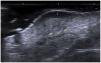

La ecografía permite la caracterización y diferenciación de masas de tejidos blandos superficiales3. Diago et al. encontraron 4 patrones de invasión ecográfica del DFSP, con una buena correlación histopatológica. El patrón más común (53,3%), igual que en nuestros casos, fue la presencia de masa hipoecoica oval con unas proyecciones seudópodas o digitiformes y áreas hiperecoicas posteriores (fig. 1) que se correlacionaban con la extensión de las células tumorales y fibroblastos dispersos en el tejido subcutáneo formando el patrón característico de panal de abejas. Cabe mencionar que las proyecciones digitiformes presentan un crecimiento asimétrico e impredecible, considerándose altamente indicativas o patognomónicas. Dichas estructuras se encontraron en la mayoría de nuestros casos (fig. 2). El segundo en frecuencia fue el patrón hipoecoico oval con unas proyecciones seudópodas pero sin las áreas hiperecoicas posteriores (20%), correlacionándose con la extensión a lo largo del septo subcutáneo. Por último, describieron un patrón mixto invasivo, pero sin proyecciones profundas (16,7%) o tumores hipoecoicos ovales dérmicos/subcutáneos (10%). La ecografía presenta una tasa de sensibilidad del 81,8% y especificidad del 100% para detectar invasión profunda, con un valor predictivo positivo del 83,3%, resaltando su importancia para evaluar extensión tumoral8.

Zou et al. describieron las diferencias ecográficas entre los tumores primarios y los recurrentes. Los tumores primarios comprometen la dermis y la hipodermis (86,4%), pero no estructuras más profundas; presentan proyecciones seudópodas (50%), mientras que los tumores recurrentes tienen una morfología oval (28,4%), lobulada (22,9%) e irregular (34,3%), sin diferencia en la ecogenicidad. La hipervascularidad se observa en ambos grupos, hallazgo común en nuestros casos6.